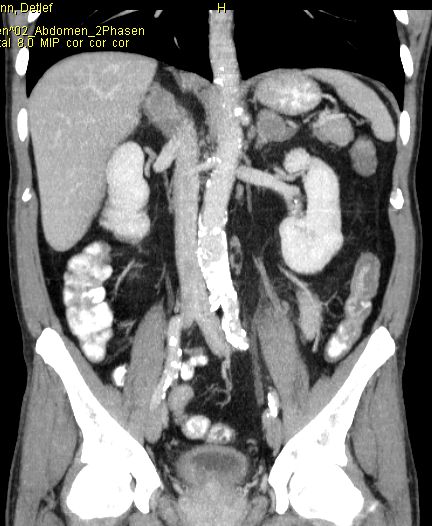

Phaeochromozytom Tumoren des Nebennierenmarks

Nebennieren - Rinden - Tumoren

Diagnostik